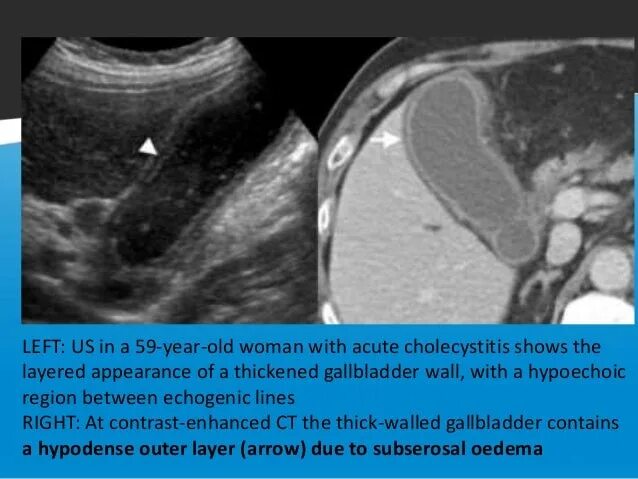

Диффузное утолщение стенок